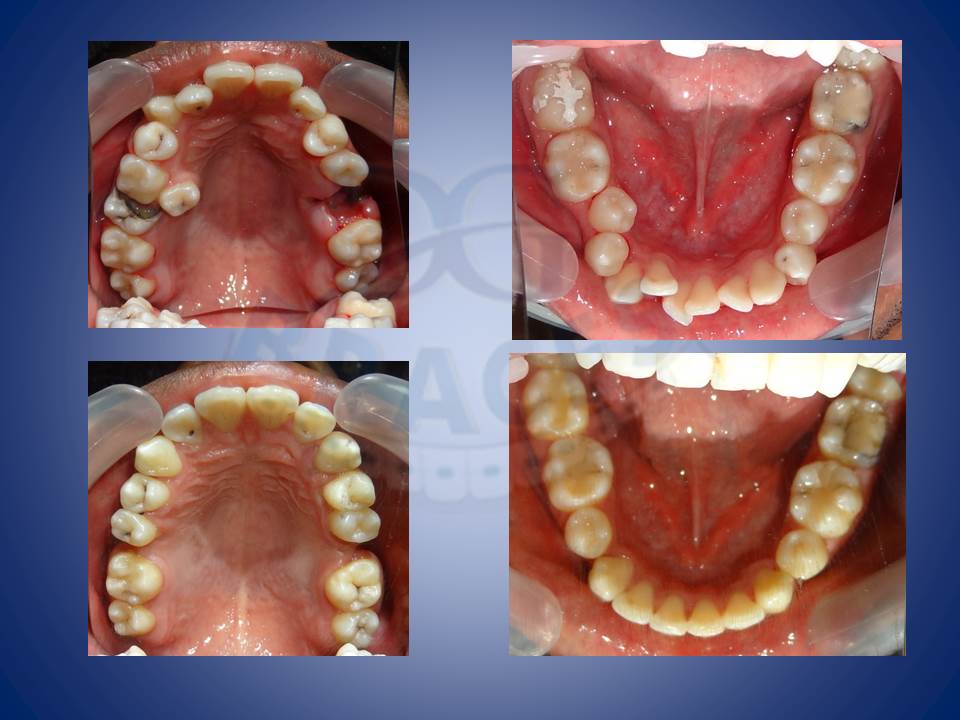

2.Crowding and multiple mutilated teeth are best left treated helping maintainance easy and improving the biting efficiency of patients upto 80%